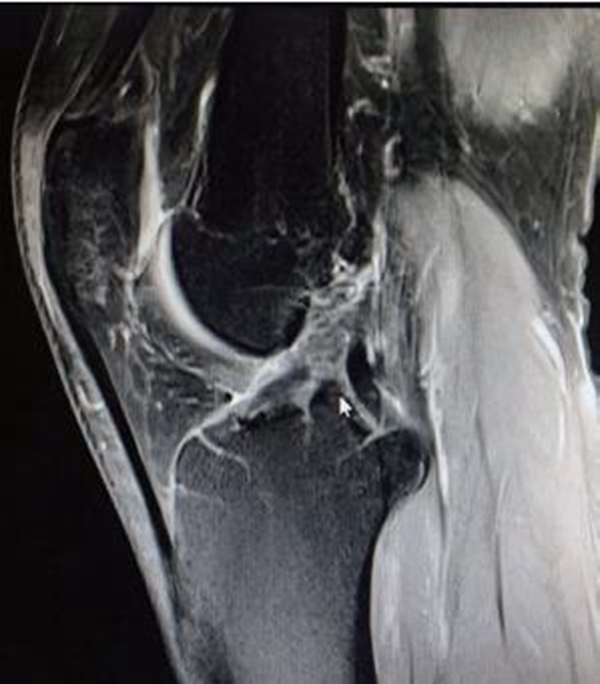

由于ACL的解剖特点,常规MRI扫描方向无法满足精确诊断的需要,因此沿ACL的方向扫描对于诊断有重要的作用。MRI影像上正常的ACL是起自股骨外侧髁内侧面,斜向前内侧走行,止于胫骨髁间隆起前方的一条边缘清晰、光滑、具有张力感的低信号带(图7)。连续性中断是ACL断裂最直观的表现(图8)。

Lee等提出ACL断裂的MRI诊断标准: ①ACL前缘呈不规则波浪状;②T2WI成像中ACL信号内有高信号;③矢状面上ACL信号不连续;④当伴有上述征象之一时,前部呈弓状的PCL可支持ACL撕裂。

图8 ACL断裂MRI影像

MRI检查不可作为ACL断裂的唯一诊断标准,临床上有部分ACL断裂后残端移位不明显,而是以瘢痕黏附于PCL或股骨髁的内侧面(图9)。该类情况需要临床医生对正常ACL的影像有清晰的认识,可以通过冠状位和矢状位上ACL的方向和角度来辨别,更重要的是与临床体格检查及病史三者结合以诊断。

图9 ACL断裂后断端移位不明显的MRI影像